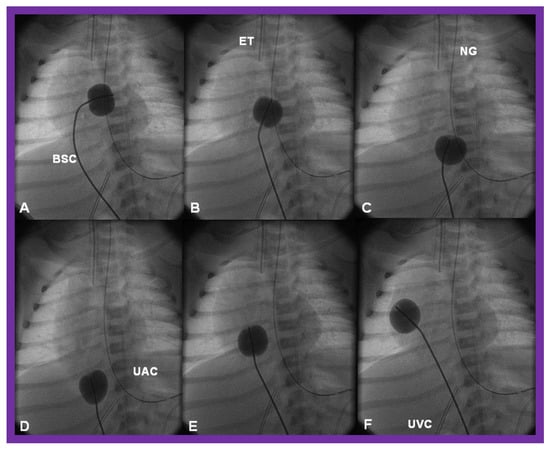

There is a tendency for the PFO to remain open because of a persistence of fetal flow patterns. However, sometimes the PFO becomes obstructed. Evidence for obstructed PFO may be present either with systemic or pulmonary venous congestion and is confirmed by a small-sized PFO by 2-dimentional echo and high velocity flow across it by Doppler studies. The PFO may be enlarged by balloon atrial septostomy (Figure 12) [52]. Such a procedure is usually successful, especially in the early neonatal period, because the septum primum (lower margin of the PFO) is thin and flail and can be ruptured by balloon septostomy.

Figure 12.

Cinfluroscopic frames demonstrating the procedure of Rashkind’s balloon septostomy. Initially the balloon is inflated in the left atrium (A). The balloon septostomy catheter (BSC) is rapidly and forcefully pulled into the right atrium (B) and inferior vena cava (C,D) and quickly advanced back into the right atrium (E,F). The entire procedure is done as one single motion. Rapid advancement of the BSC into the right atrium (E,F) is done in order to avoid inadvertent occlusion of the inferior vena cava if failure to deflate the balloon occurs (this is quite rare). At about the same time the balloon is deflated. ET, endotracheal tube; NG, nasogastric tube; UAC, umbilical arterial catheter; UVC, umbilical venous catheter.

When PFO obstruction develops during the later part of the neonatal period or in older infants, balloon atrial septostomy is unlikely to be successful, and in such situations, alternative methods such as blade atrial septostomy [53], static balloon dilatation [54,55], or stent placement [56,57,58] may have to be used to accomplish the relief of inter-atrial obstruction. If transcatheter methods are not feasible or not successful, surgical atrial septectomy is necessary. If there is no PFO and the atrial septum is intact, the atrial septum may be perforated either by Brockenbrough technique [59] or radiofrequency perforation [60]. This should be followed by static dilatation [54,55] or stent placement across the atrial septum [56,57,58]. For a detailed discussion of these transcatheter techniques, the interested reader may review the author’s previous publications [58,61].